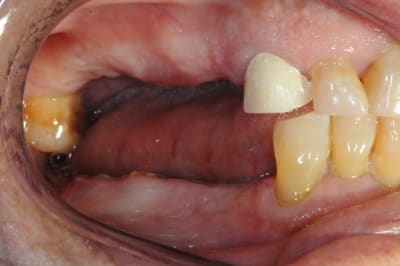

charlie est un blanchiment interne + compo palatin

rien en vestibulaire à part blanchiment complémentaire (à la base la dent nécrosée était vraiment très foncée)

la photo est à l'envers

Mais sinon vous avez tous raison : c'est bien la 21 (donc 41 pour D57) sauf toi Jeamba qui as eu une hésitation : tu étais plus proche avec ta 12 en verlan

technique : perborate 2 séances (3 jours à chaque fois) puis compo teinte bleaching dans la cavité et une séance de zoom en complémentaire externe